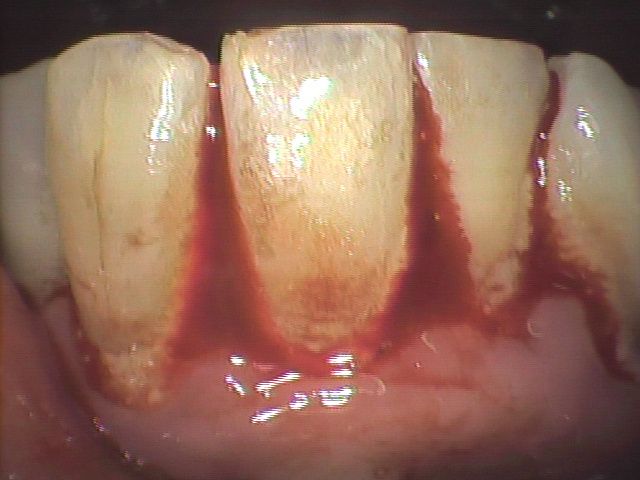

仮固定はタイムリーに実施しますと非常に有効な処置にもかかわらず、ここ十数年の間で重症になられてFDCに転医されている患者さんには、なぜかこの処置をおこなった形跡が見あたらないようです。以下に示します症例はCT読影の結果、歯槽骨の吸収が著しく、そのため強度の歯の動揺、さらに出血も相当ありました。

しかし、仮固定と共に歯周ポケットの「病原菌除菌」とレーザー治療などによる歯周組織の「ダメージ回復」を統合的に実施しますと短期間で病状が改善し咀嚼も普通にできるようになっています。(Photo.4-1, Photo.4-2)

また、(Photo-5.1)ならびに(Photo-5.2)の症例はいずれも末期の歯周病で歯の動揺も大きく、さらに排膿や腫れが見られ抜歯が必要でした。しかし、同様の処置を行ない仮固定の交換のみで初診時の症状は解消し、すでに7年間経過しています。抜歯に該当する歯であっても仮固定で支え、FDC治療システムと熱心なホームケアによって歯を残すことが可能です。